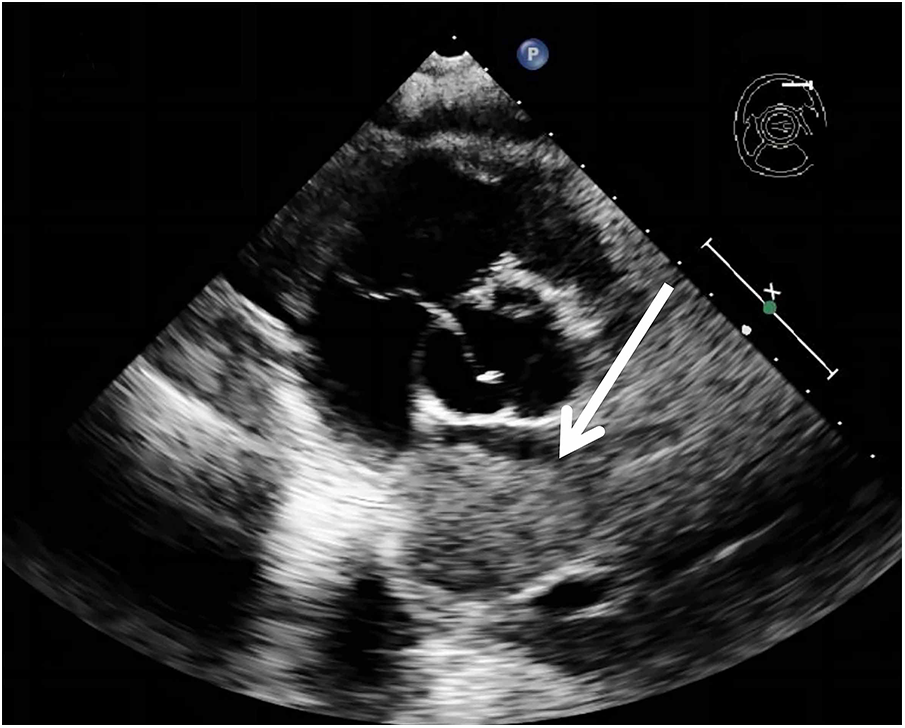

A 62-year-old non-smoking female presented to our hospital with kidney stones and underwent a comprehensive full-body examination. She self-reported being previously healthy and not experiencing any symptoms, except for a significant recent weight loss. During the physical examination, the patient appeared to be in good overall condition, with a blood pressure reading of 92/51 mmHg, a heart rate of 81 beats per min, a respiratory rate of 19 breaths per min, and no murmurs detected upon cardiopulmonary auscultation. The chest CT scan revealed lung cancer in the upper lobe of the right lung, which was further complicated by hilar and mediastinal lymph node metastasis. The lymphatic vessels surrounding the tumor appeared thickened and nodulated. Transthoracic echocardiography and organ acoustic imaging identified a 5.1 × 3.4 cm metastatic hypoechoic mass in the left atrium, closely associated with the right pulmonary vein (Figure 1). She underwent additional CT contrast imaging of the neck, chest, and upper abdomen, which confirmed the presence of a mass in the left atrium connected to the right upper pulmonary vein (Figure 2). Furthermore, a metastatic nodule was detected in the right adrenal gland. Simultaneously, a contrast-enhanced MRI of the head revealed a circular enhancing nodule located centrally within an oval lesion on the left side, indicative of skull metastasis. To elucidate the pathology, the patient ultimately opted for lung biopsy and immunohistochemical examination, which confirmed the diagnosis of non-small-cell lung cancer (NSCLC). Microscopic examination revealed cancer cells arranged in nests and clusters, demonstrating infiltrative growth, notable heterogeneity among the cancer cells, and proliferation of interstitial fibrous tissue (Figure 3). Following antigen retrieval, blocking, antibody staining, and color development steps in immunohistochemistry, the results indicate that the cancer cells exhibited positivity for CK, focal positivity for CK7, TTF1 (localized), and PD-L1 22C3 TPS (localized), with a Ki-67 proliferation index of approximately 20%. The cells tested negative for NapsinA, P40, P63, CK5/6, and ALK-D5F3. Special stains indicated negative staining for mucus carmine and positive staining for individual cells of AB-PAS.

Figure 1

A metastatic hypoechoic mass, measuring 5.1 × 3.4 cm, was present in the left atrium, closely adjacent to the right pulmonary vein.